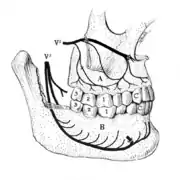

A tooth is composed of an outer shell of calcified hard tissues (from hardest to softest: enamel, dentin, and cementum), and an inner soft tissue core (the pulp system), which contains nerves and blood vessels. The visible parts of the teeth in the mouth – the crowns (covered by enamel) – are anchored into the bone by the roots (covered by cementum). Underneath the cementum and enamel layers, dentin forms the bulk of the tooth and surrounds the pulp system. The part of the pulp inside the crown is the pulp chamber, and the central soft tissue nutrient canals within each root are root canals, exiting through one or more holes at the root end (apical foramen/foramina). The periodontal ligament connects the roots to the bony socket. The gingiva covers the alveolar processes, the tooth-bearing arches of the jaws.[42]: 1–5